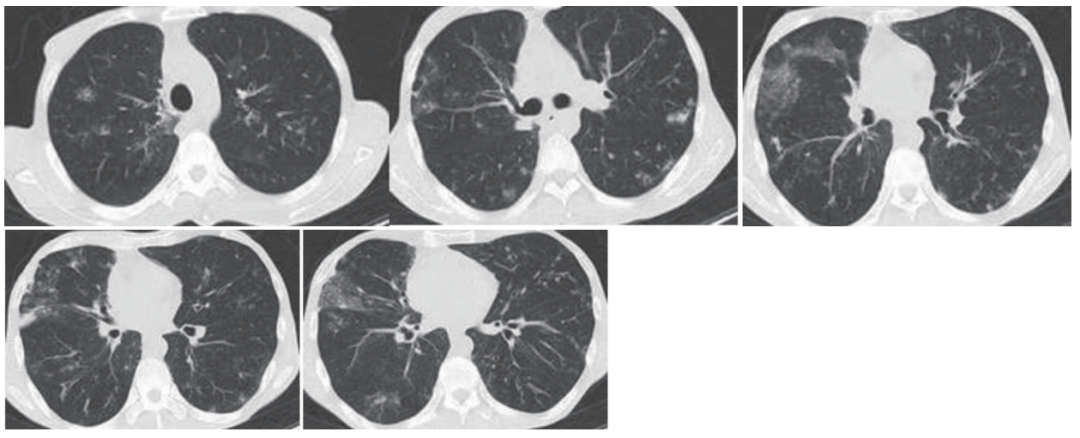

2月前患者自觉活动后气短明显加重,复查胸部CT示双肺炎性病变可能、较前部分新发,范围扩大(图1)。遂于我院住院治疗,气管镜肺泡灌洗液检出诺卡菌、黄曲霉菌,予以复方磺胺甲噁唑联合伏立康唑抗感染治疗1月余,咳嗽、咳痰症状减轻,呼吸困难基本改善。复查胸部CT示双肺炎症病变明显吸收(图2),出院后继续口服复方磺胺甲噁唑伏立康唑抗感染治疗。

图1 胸部CT(2024年7月)